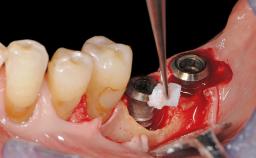

A 72-year-old female patient was referred to the specialist clinic with signs of peri-implantitis associated with implant 14. Two implants (sites 14 and 15) had been in function for three years. The patient was in good general health and was not taking any medication. She was a former smoker (12–15 cigarettes a day for 50 years) but had ceased smoking two years prior to implant placement. Her periodontal condition was stable, with no probing depths above 5 mm and a full-mouth plaque score (FMPS) of 35%.